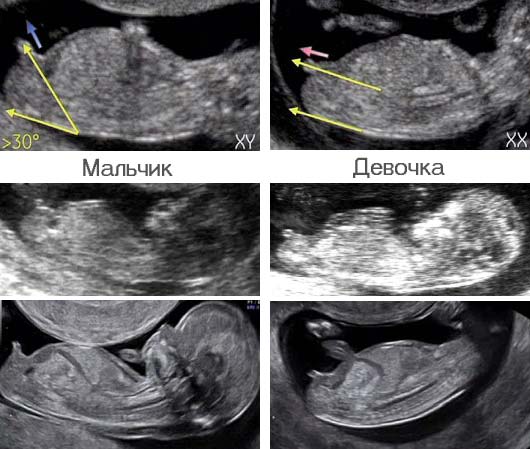

Итак ножки мы скрестили)) пол не показали и ждём второго скрининга)) Нутром почему то настроена на мальчика)

Более вероятно, что девочка. Если бы был мальчик, то у них писюн смотрит вверх, и с такого ракурса уже был бы виден. 😊

Так ножки же крестиком, как может быть видно?

Врач сказал ещё одинаковые в 12 недель ))

Поверьте мне, разные у них писюны в 12 недель. Мне в 12+1 сразу сказали девочка (ногу на ногу поставила, но все равно увидели), да я и сама видела писюн параллельно телу (это девочка). А у подруги стручок смотрел вверх. Но это ведь всего мои предположения, а так, на 2м скрининге уже будет яснее. Пусть я ошибаюсь)))

Только с этой стороны, как на фото и между ног. Так как мне показывали пятки и пальчики на ногах. Но между ног было не показательно, так как там торчал писюн как у мальчиков 😅. А вот с такого ракурса, как на фото даже я увидела, что пися смотрит не вверх, а в параллельно телу.

Малыш лежит боком,как можно увидеть кто 🤷🤭 когда ноги скрещивают смотрят снизу, видимо вам просто такой врач попался